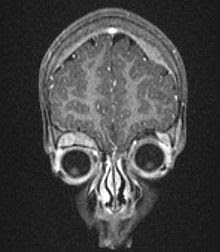

MRI showing orbital and skull vault metastatic NB in 2 year old